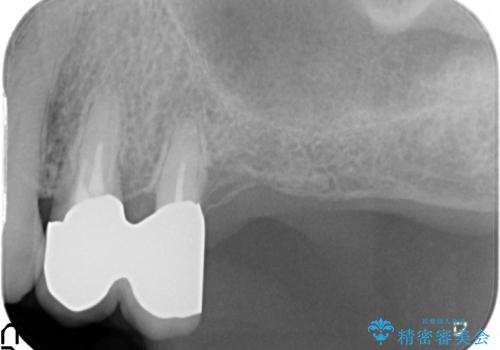

歯ぐきから血が出る、歯ぐきが腫れている 80代女性

- 歯ぐきからの出血と腫れを主訴に来院された患者様です。

プラークコントロールが非常に悪く、全顎的な歯周病に罹患していました。

「抜歯したくない、インプラントは嫌」という患者様のご希望とご年齢を考慮し、可及的な骨外科処置や根分割術によりできるだけ今ある歯を残す治療方針をたてました。

保存不可能な左上の奥歯2本(左上67)は抜去し、ノンクラスプデンチャーをいれることにしました。

歯ぐきの腫れや出血が改善され、喜んで下さいました。

プラークコントロールを徹底して頂き、できるだけ歯が長持ちするよう今後も定期検診でフォローさせて頂きます。

被せ物の種類:メタルボンドクラウン エコノミー

入れ歯の種類:ノンクラスプデンチャー